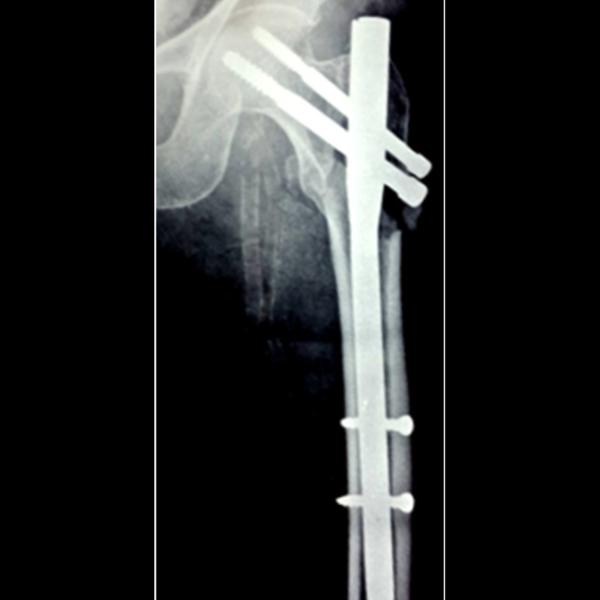

PFN NAILING SURGERY IN THANE